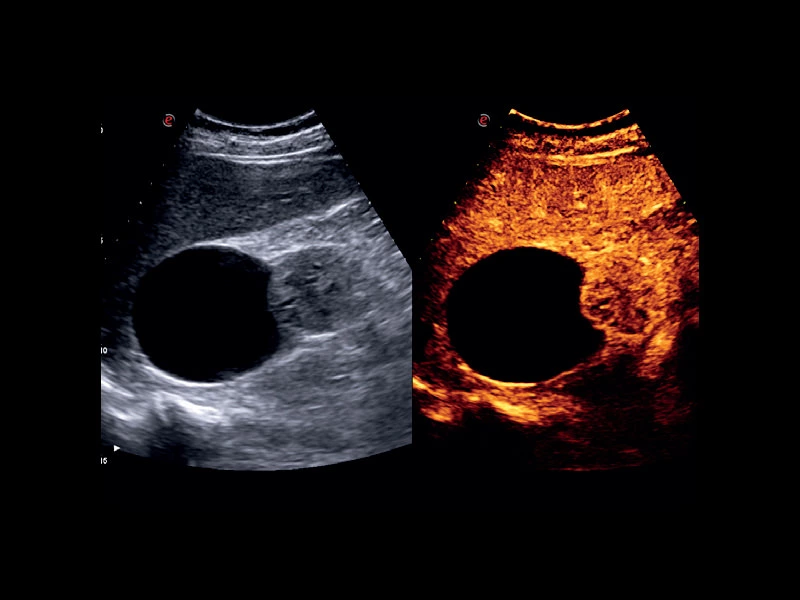

MyLab™C30 - Interventional B-Mode - Kidney

MyLab™C30 - Interventional B-Mode - Kidney